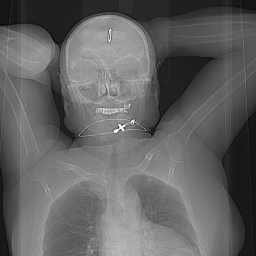

Существует приложение для смартфонов под названием e-anatomy. https://www.imaios.com/ru/e-anatomy

Приложение содержит богатый атлас по разным частям тела и органам человеческого организма. Беда в том, что подписка на этот атлас стоит вовсе небожеских денег: около 2к в месяц или 10к в год. И оплатить подписку тот ещё квест. У приложения была взломанная "бесплатная" версия 4.2. Но эта версия не устанавливается на современные смартфоны. Возможно, кто-то возьмётся бесплатно или за вознаграждение обработать существующую версию до "бесплатной"?)